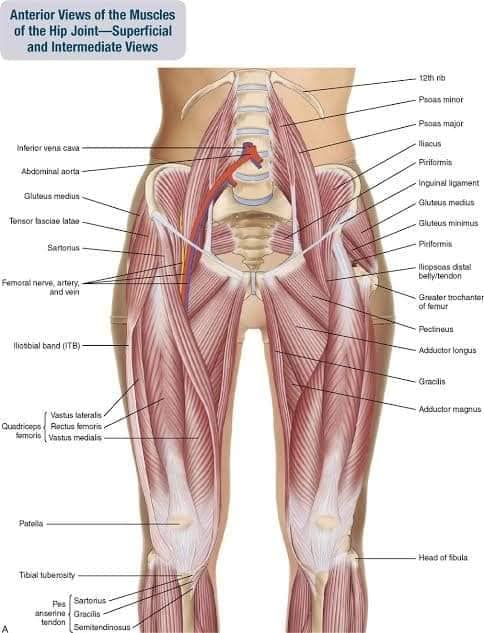

Спинні м'язи виконують функції підтримки хребта, а також дозволяють здійснювати рухи тулуба.

Глибинні спинні м'язи

М'язи, що забезпечують стабільність хребта: М'язи, що розташовані між хребцями: включають мускулатуру, яка забезпечує стабільність і підтримку хребта, а також дозволяє здійснювати рухи хребта.

М'язи, що здійснюють ротацію та нахили

М'язи, що забезпечують ротацію хребта: Ротаційні м'язи: допомагають у здійсненні обертальних рухів тулуба, а також у підтримці рівноваги і стабільності хребта.